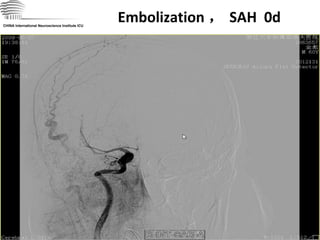

Embolization , SAH  0d CHINA International Neuroscience Institute ICU